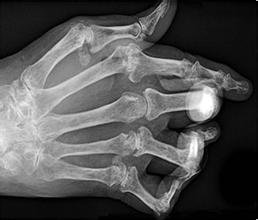

类风湿是类风湿性关节炎的简称,是一种以关节滑膜炎为特征的慢性全身性自身免疫性疾病。滑膜炎持久反复发作,可导致关节内软骨和骨的破坏,关节功能障碍甚至残废,血管炎病变累及全身…「查看详情」

生活中类风湿的发病率是很高的,不慎出现类风湿了,一定要及时诊断治疗,否则就会造成许多严重的伤害。下面一起来看看类风湿会造成什么伤害,希望能引起大家的重视。…「查看详情」

类风湿性关节炎是临床上较常见的关节疾病,多发生在中老年人身上。济南中德骨科医院专家提醒大家,出现类风湿性关节炎了要及早治疗,避免给身体带来危害。下面就来看看类风湿性关节炎…「查看详情」